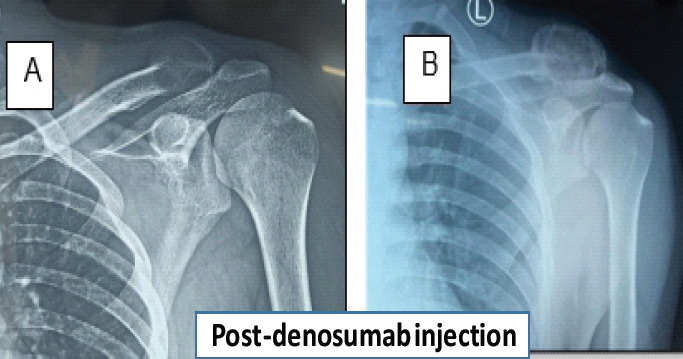

Case report: A young male patient comes with lateral end clavicle swelling, which on radiologically was diagnosed giant cell tumor. Later on, needle biopsy was thought to be an aneurysmal bone cyst (ABC). Finally, it turned out to be CMF on biopsy.

Conclusion: This case report presents a rare instance in which CMF was initially misdiagnosed as a giant cell tumor based on radiological findings and later as an ABC after histopathological examination. The definitive diagnosis of CMF was only confirmed following excisional biopsy.